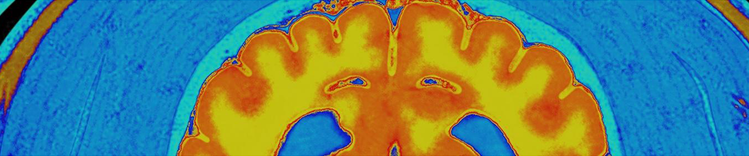

NEURONENMASSE UND HIRN-MRT

Veränderungen im alternden Gehirn

Zu den physischen Veränderungen des Gehirns, die mit dem Altern einhergehen, gehören:

- Atrophie (Schrumpfung) des Gewebes in einigen Regionen

- erhöhtes Ventrikelvolumen

- Verlust von Neuronen und Synapsen und verminderte Bildung neuer Neuronen

- Anhäufung von abnormen Proteinen